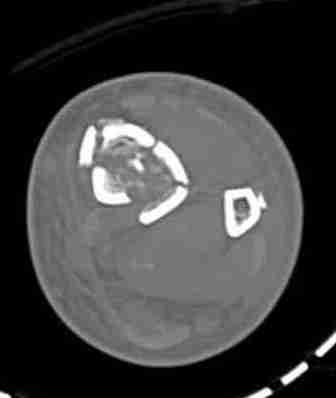

При высокоскоростных переломах редко можно встретить изолированную травму пилона, и в моей практике изолированные травмы большая редкость, поэтому, как дополнение к обсуждаемой теме, решил представить свежий, двухдневной давности случай.

Предыдущей сменой до 4:00 утра по поводу открытого перелома бедра, тибиал плато, пилон и надколенника сделана операция.

Пострадавшему 21 г., травма скоростная, после I&D с расширением раны, на бедре сделана операция ретроградным интрамедуллярным штифтом, остеосинтез с частичной резекцией надколенника и ушивание собственной связки.

На голень наружный фиксатор, рану на бедре ушили (рана была изнутри кнаружи всего 2 см). По протоколу травматических больных, до операции обследован ангиографически, (у больного дистально не смогли определить пульсацию) сосудистый хирург подтвердил проходимость на всем протяжении магистрального сосуда нижней конечности по снимкам ангиограмм.

КТ пилона имеем.